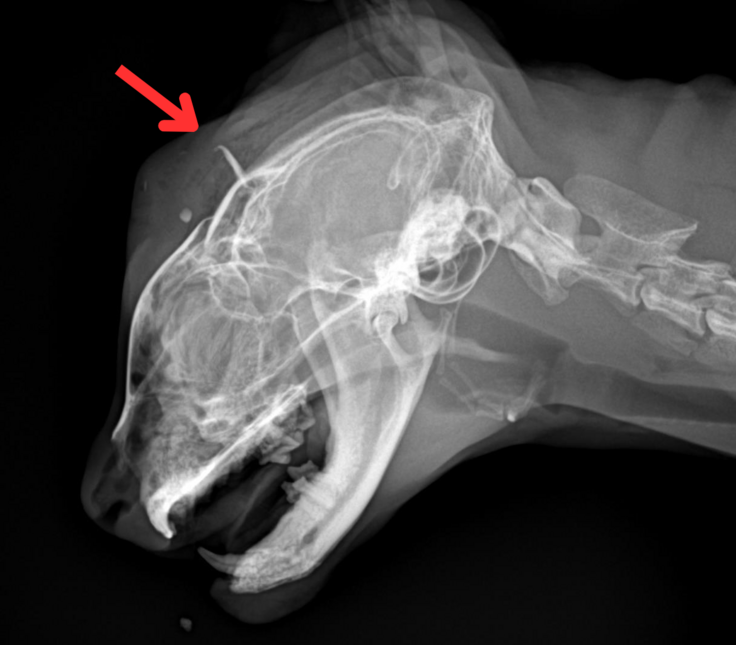

レントゲン検査の結果、頭蓋骨の骨折が確認され、呼吸も早く、肺出血(肺挫傷)の可能性も高いという、非常に危険な状態でした。

【事故直後のレントゲン写真:頭蓋骨に骨折がある】